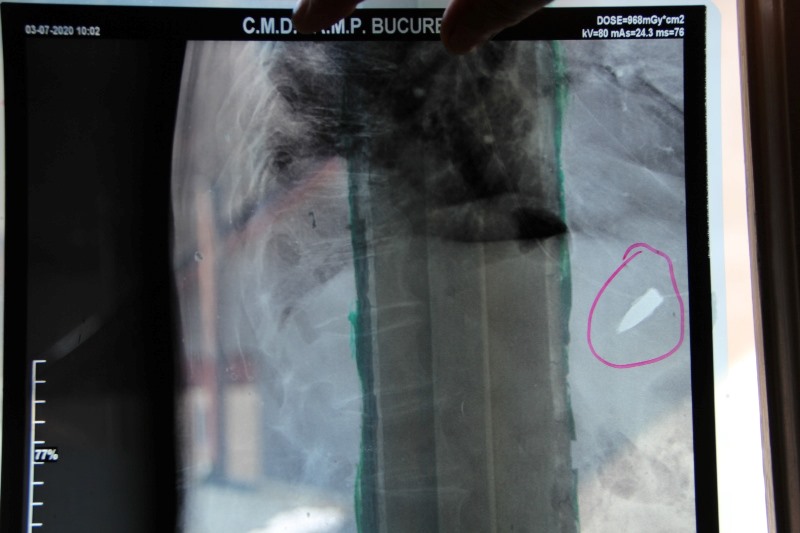

A fost împușcat în cel de-al Doilea Război Mondial, iar de opt decenii trăiește cu un glonț, fixat în vecinătate inimii, cu care s-a ales în luptele contra rușilor. Organismul i l-a acceptat.

Ori de câte ori este întrebat de momentele trăite la ruși, nu omite episodul în care a fost „vizitat“ de moarte și în care s-a trezit cu un glonț în spinare. Un glonț care i-a perforat plămânul și i-a ajuns lângă inimă. A fost scos din tabăra de luptă și târât de ceilalți soldați pe o poiană de unde a fost preluat de sanitari.

Odată cu terminarea războiului a revenit la „vatră“, unde și-a regăsit familia și unde mama sa, care era și moașă, cunoștea tot rostul plantelor și era știută în zonă ca având „leac“, i-a fost principalul medic. L-a îngrijit până i s-a închis rana și a putut respira neîntrerupt. De scos glonțul, medicii s-au opus rând pe rând, spunându-i că i-ar face mai mult rău.